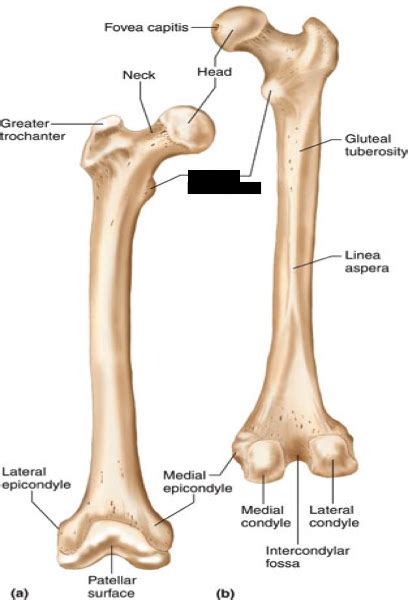

The shaft of the femur is gradually convex anteriorly with maximum convexity in the middle third where the shaft is narrowest. Caption2 = upper extremity of right femur viewed from behind and above. Here the two trochanters, greater and lesser trochanter, are found. The lesser trochanter is a feature of the femur, the large long bone of the upper leg that spans from the hip to the knee. The position of the lesser trochanter close to the head of the femur is one of the defining characteristics of the prozostrodontia.

The lesser trochanter is a small protuberance of bone that projects from the posterior aspect of the femur, inferomedially at the base of the femoral neck. Upper extremity of right femur viewed from behind and above. It projects from the lower and back part of the base of the femur neck. Over 65000 hip fractures each year are recorded occur in the uk alone and they are neck of femur (nof) fractures can occur anywhere from the subcapital region of the femoral head to 5cm distal to the lesser trochanter (fig. anterior view / right femur lesser trochanter (trochanter minor) is a medial prominence located just inferior to neck. Ebraheim's educational animated video describes anatomy and how to draw the femur. Abducts and medially rotates the thigh at hip more vertical alignment. Inclusion criteria included unstable trochanteric femur fractures with displaced lesser trochanter treated by proximal femoral nail (pfn), proximal. Femur is bone that extends from hip to knee joint and is also called thigh bone. The greater trochanter gives attachment to a number of muscles (including the gluteus medius and minimus, piriformis, obturator internus and externus, and gemelli muscles). The shaft of the femur is gradually convex anteriorly with maximum convexity in the middle third where the shaft is narrowest. Subscribe to learn interesting facts about the human body every day. A pyramidal process projecting from the medial and proximal part of the shaft of the femur;

The upper end of the femur includes the head, the neck, the greater trochanter, the lesser trochanter, the intertrochanteric line, and the intertrochanteric crest.

The lesser trochanter (small trochanter) of the femur is a conical eminence, which varies in size in different subjects. The lesser trochanter (trochanter minor; It is the insertion point for the iliacus and psoas major muscles. The lesser trochanter is a small protuberance of bone that projects from the posterior aspect of the femur, inferomedially at the base of the femoral neck. Two of these are above—a medial continuous with the lower border. The lesser trochanter is also called the minor trochanter, the inner trochanter, and the medial process of the femur. It receives the insertion of the psoas major and there are 2 trochanters (greater and lesser) both are prominences found on the upper aspect of the femur (thigh bone) between the shaft and neck. It projects from the lower and back part of the base of the femur neck. A pyramidal process projecting from the medial and proximal part of the shaft of the femur; Musclesorigins = musclesinsertions = psoas major articulations = meshname = meshnumber = dorlandspre = t_20 dorlandssuf = 12824961 the lesser trochanter (small trochanter) of the femur is a conical. Upper extremity of right femur viewed from behind and above. Ligamentum teres femoris connects the acetabulum to the fovea capitis femoris (a pit on the at the base of the neck are the medially oriented lesser trochanter and laterally placed greater trochanter. The greater and lesser trochanters serve as a muscle attachment sites for the tendons of many powerful muscles of the hip and groin such as the the trochanters also widen and strengthen the femur in a critical region of high stresses due to external trauma and the force of muscle contractions.